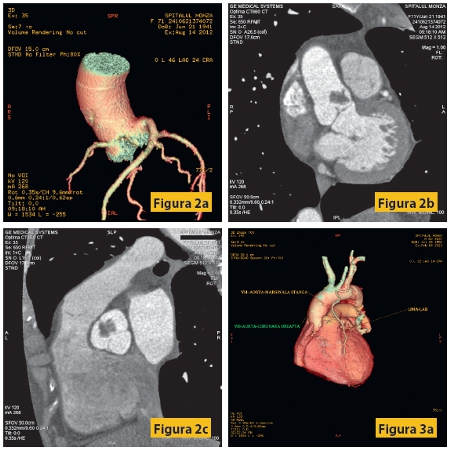

Figura1: Pacient M, 63 ani, cunoscut cu anevrism gigant de aortă ascendentă toracală, cu insuficienţă aortică severă, insuficienţă ventriculară stângă de repaus, HTA şi dislipidemie. Examinarea angiocoronaro-CT evidenţiază dilataţie anevrismală importantă a aortei ascendente, inclusiv a rădăcinii aortice, circulaţie coronariană cu dominanţă stânga, cu aspect hipoplazic al arterei coronare drepte. Fără stenoze semnificative la nivel coronarian.

Figura 2: Pacient F, 71 ani, cunoscută cu proces expansiv de valvă aortică, cu anevrism septal interatrial permeabil, HTA stadiul II. Examinarea angiocoronaro-CT efectuată înaintea intervenţiei chirurgicale arată o circulaţie coronariană cu dominanţă stânga, fără stenoze semnificativă la nivelul arterelor coronare, precum şi procesul expansiv de la nivelul valvei (defect de umplere cu contururi neregulate, cu dimensiuni maxime de 16/13 mm, localizat la nivelul valvei aortice cu infiltrarea cuspei drepte).Examenul histopatologic a stabilit diagnosticul de fibroelastom.

Figura 3: Pacient M, 60 ani, cunoscut cu by-pass aortocoronarian, cu dureri anginoase reapărute în ultimile 4 luni, cu multipli factori de risc cardio-vasculari: diabet zaharat, hipertensiune arterială, dislipidemie. Examinarea coronarografică nu poate preciza cu exactitate permeabilitatea graftului cu artera marginală stânga, care apare opacifiat, cel mai probabil prin umplere retrogradă.

La examenul angiocoronaro-CT se evidenţiază graft LIMA-LAD (artera marginală inferioară stângă - artera descendentă anterioară stângă) permeabil, GRAFT-AORTĂ-MARGINALĂ STÂNGA trombozat, VSI-AORTĂ-CORONARĂ DREAPTA bont închis la nivelul aortei, precum şi un stent patent la nivelul ramului intermediar.